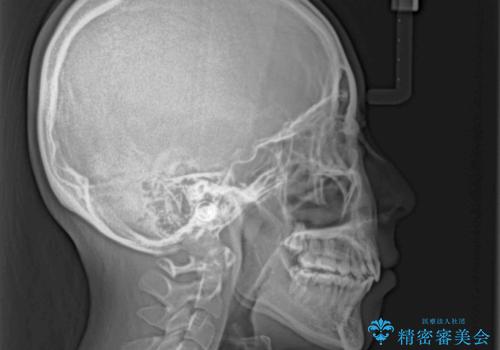

ディープバイトは、治療を行っていた我々も驚くほど、短期間で劇的に改善することができました。

骨格的に下顎骨が左側にシフトしていたため、上下正中の位置や左側臼歯部の咬合を理想的に仕上げることはできませんでしたが、非常に綺麗な口元を達成することができました。